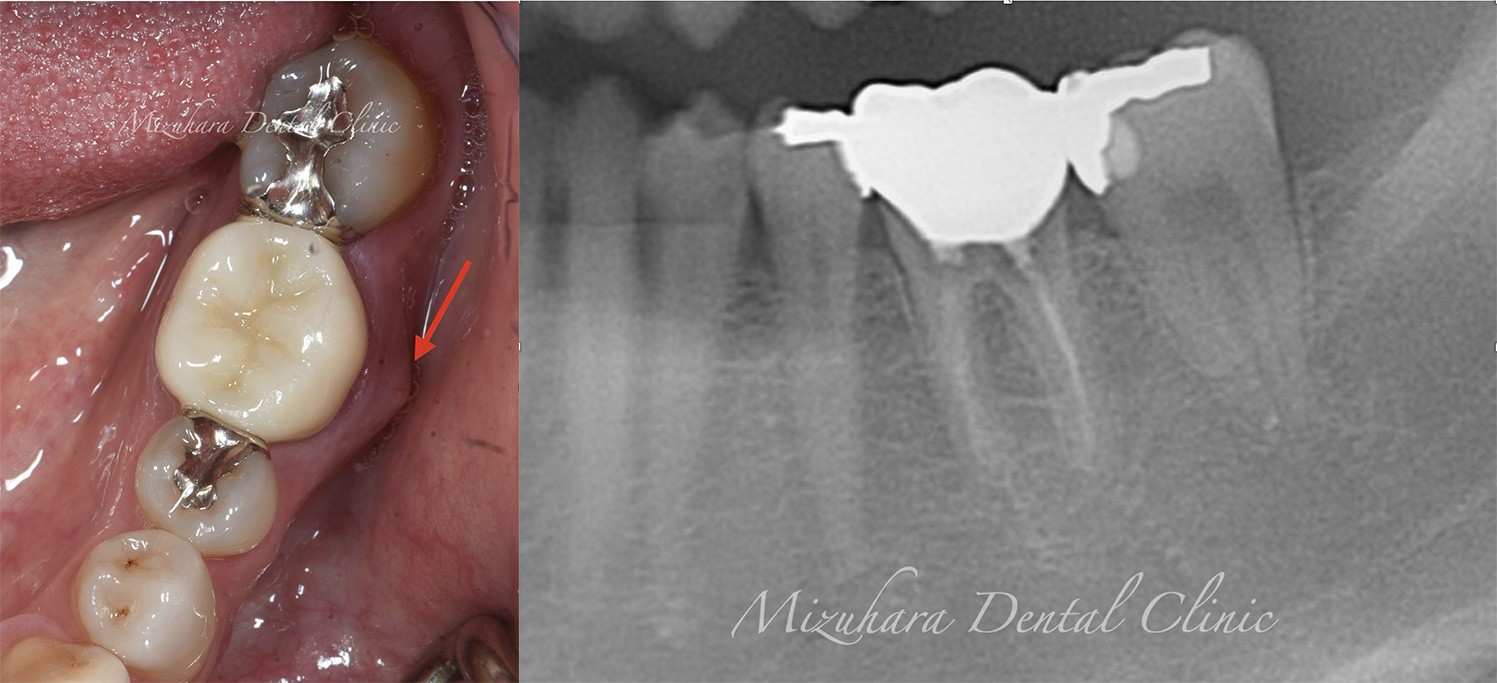

CASE

症例紹介

三鷹の歯医者【みずはら歯科・矯正歯科 三鷹】